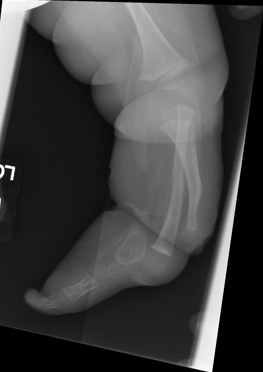

Leg short +++

Tibial Anterolateral Bowing

Foot fixed in severe varus

Knee

- FFD

- may be unstable

- no quads mechanism